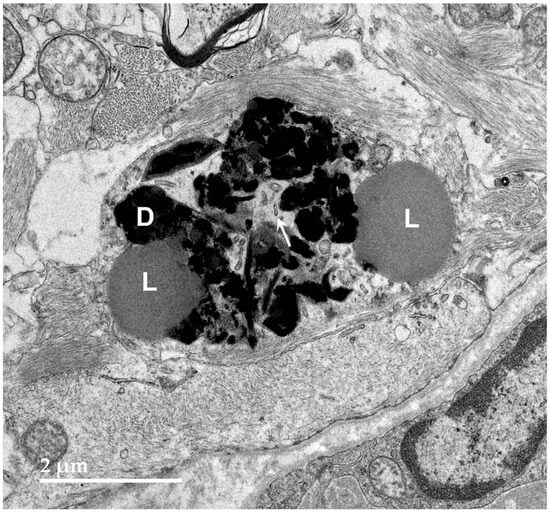

3.1. Microscopic Findings